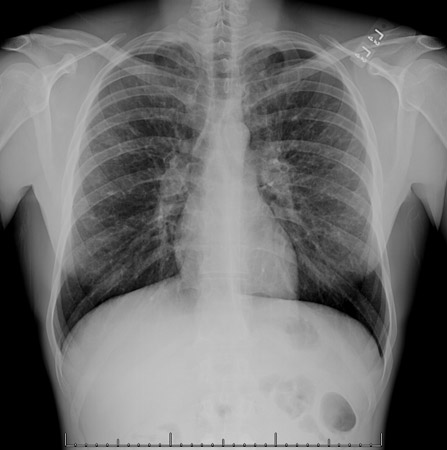

Uma radiografia torácica deve ser obtida no início da avaliação da tosse crônica.[38] Embora não seja diagnóstica das causas mais comuns, os achados podem facilmente desviar a avaliação para causas de maior gravidade como doenças pulmonares estruturais. Eles incluem câncer pulmonar, fibrose pulmonar, tuberculose, bronquiectasia, pneumonia, aspiração e sarcoidose.[Figure caption and citation for the preceding image starts]: Radiografia torácica mostrando hiperinsuflação em paciente com DPOC. A hiperinsuflação é causada pelo componente de enfisema na DPOC, em vez da bronquite crônica subjacente aos sintomas da tosseDo acervo pessoal do Dr. M. A. Sharifabadand, SUNY na Stony Brook School of Medicine, Departamento de Medicina Pulmonar e Intensiva, Mineola, Nova York, e Dr. J. P. Parsons, The Ohio State University Medical Center, Columbus; usado com permissão [Citation ends].

[Figure caption and citation for the preceding image starts]: Radiografia torácica mostrando múltiplas metástases pulmonares miliares (setas). O tumor primário era carcinoma de tireoideE. Dick, Student BMJ. 2001;9:10-12 [Citation ends].